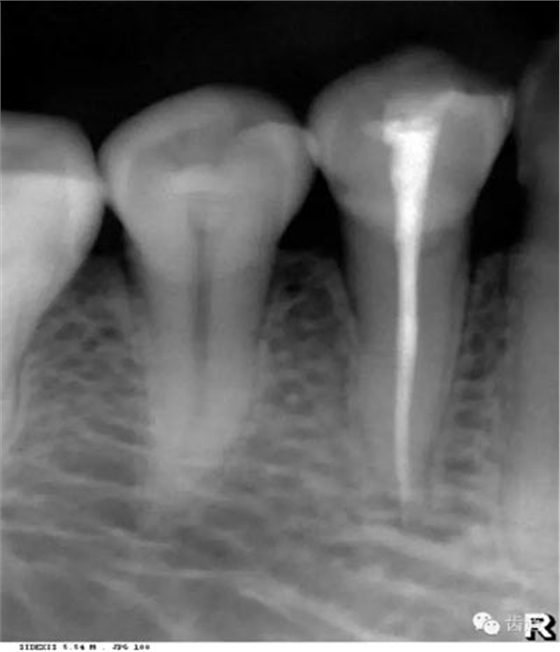

髓腔可分為冠部的髓室和根部的根管。牙髓內(nèi)含牙髓軟組織,X線片上顯示為密度低的影像。年輕人的牙、牙根未完全形成時(shí),根尖孔粗大,牙髓腔大。隨著年齡的增長(zhǎng),牙本質(zhì)逐漸增多,髓腔愈狹窄,根尖逐漸變細(xì)。

即固有牙槽骨,是牙槽骨的內(nèi)壁,圍繞牙根,骨質(zhì)致密而薄,X線片上顯示為包繞牙根的連續(xù)不斷的密度高的線條狀影像。

是介于牙槽窩和牙骨質(zhì)之間的結(jié)締組織。牙周膜的厚度一般在0.15~0.38mm之間。X線上顯示為包繞牙根連續(xù)不斷的密度低的線條狀影像,其寬度均勻一致